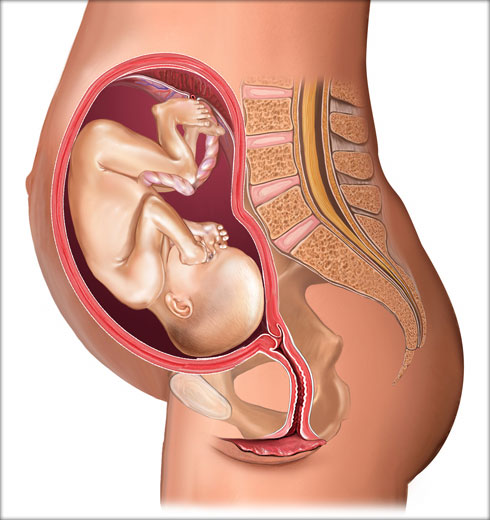

Развој бебе у стомаку мајке

од зачећа 28 недеља